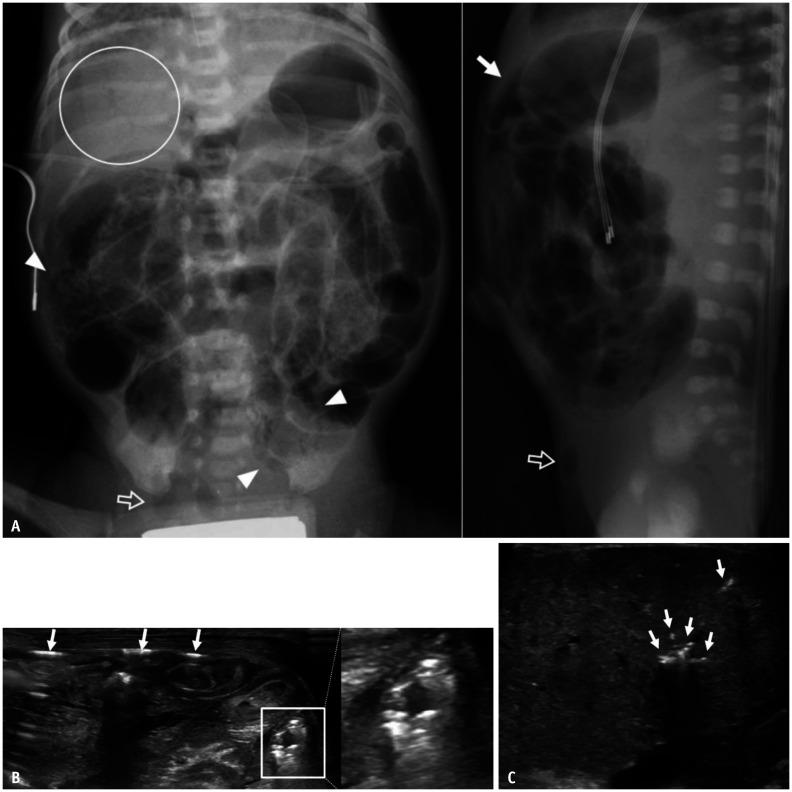

Gastrointestinal (GI) emergencies in neonates and infants encompass from the beginning to the end of the GI tract. Both congenital and acquired conditions can cause various GI emergencies in neonates and infants. Given the overlapping or nonspecific clinical findings of many different neonatal and infantile GI emergencies and the unique characteristics of this age group, appropriate imaging is key to accurate and timely diagnosis while avoiding unnecessary radiation hazard and medical costs. In this paper, we discuss the radiological findings of essential neonatal and infantile GI emergencies, including esophageal atresia and tracheoesophageal fistula, hypertrophic pyloric stenosis, duodenal atresia, malrotation, midgut volvulus for upper GI emergencies, and jejunoileal atresia, meconium ileus, meconium plug syndrome, meconium peritonitis, Hirschsprung disease, anorectal malformation, necrotizing enterocolitis, and intussusception for lower GI emergencies.

新生儿和婴儿的胃肠道(GI)急症涵盖了从胃肠道的开始到结束的各个方面。先天性和后天性疾病都可能导致新生儿和婴儿出现各种胃肠道急症。鉴于许多不同的新生儿和婴儿胃肠道急症的临床发现具有重叠或非特异性,以及该年龄段的独特特征,适当的影像学检查对于准确和及时的诊断至关重要,同时避免不必要的辐射危害和医疗费用。在本文中,我们讨论了基本的新生儿和婴儿胃肠道急症的放射学表现,包括食管闭锁和食管气管瘘、肥厚性幽门狭窄、十二指肠闭锁、肠旋转不良、胃上消化道急症,以及空肠回肠闭锁、胎粪性肠梗阻、胎粪栓综合征、胎粪性腹膜炎、先天性巨结肠、肛门直肠畸形、坏死性小肠结肠炎和肠套叠等下消化道急症。